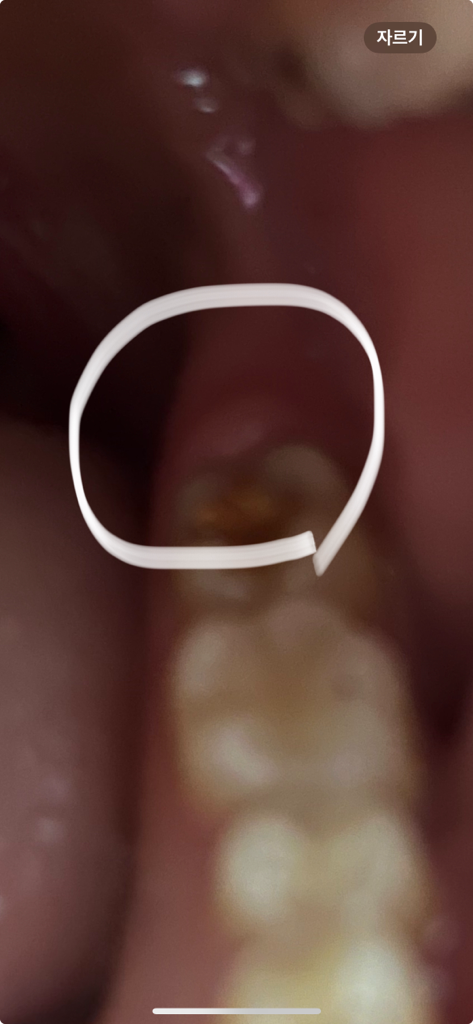

어금니 뒤쪽으로는 사랑니가 나는 자리이고 해당 부위의 부종이나 통증은 사랑니가 연관되어있을 수 있겠습니다. 치과를 방문해보시기 바랍니다.

관련 전공이 아니라 조심스럽지만. 개인적인 생각으론

말씀하신 대로 사랑니 관련 염증일 수도 있고

옆의 어금니도 컨디션이 좋아보이지 않는데.. 그로인한 영향일 수도 있을 듯 합니다